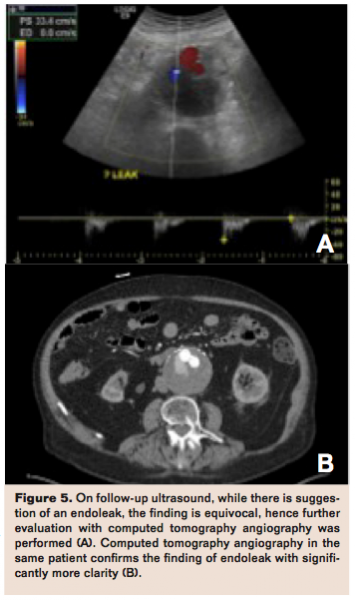

Previously performed studies have demonstrated excellent correlation between CT and ultrasound for aneurysm sac size after EVAR.31,32 However, both studies demonstrated limited agreement between actual measurements of AAA diameter between US and CT, with US underestimating AAA diameter compared to CT between 1.8 and 2.9 mm.31,32 In addition, for AAA diameter change, one of these studies showed that in 23% of cases of AAA repair, US demonstrated diameter change that would have influenced patient management, while CT did not demonstrate changes in these cases.31 Finally, while US demonstrates excellent specificity for endoleak detection (91% to 93%), sensitivity is limited (66% to 69%) (Figure 5).33,34 While US may have some role for AAA follow-up following EVAR, one reason CT has persisted in the follow-up regimen for EVAR is the demand for precise, reproducible aneurysm size measurement.29